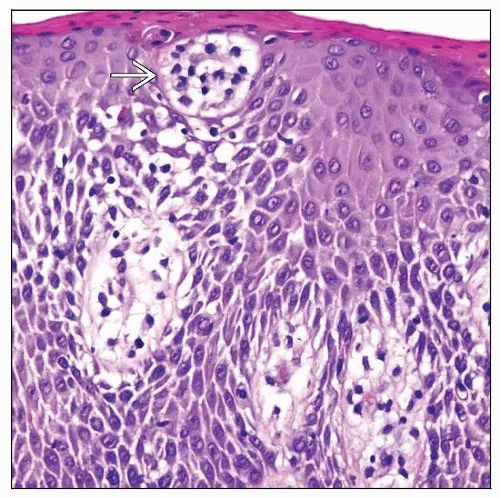

- Histology: Pautrier's microabscesses-intraepidermal nests of neoplastic CD4+ T-cells with cerebriform nuclei.

ā The "starry sky" in Burkitt's is formed by tingible body macrophages (stars) engulfing apoptotic tumor cells amidst a sheet of dark, uniform lymphoid cells (sky).